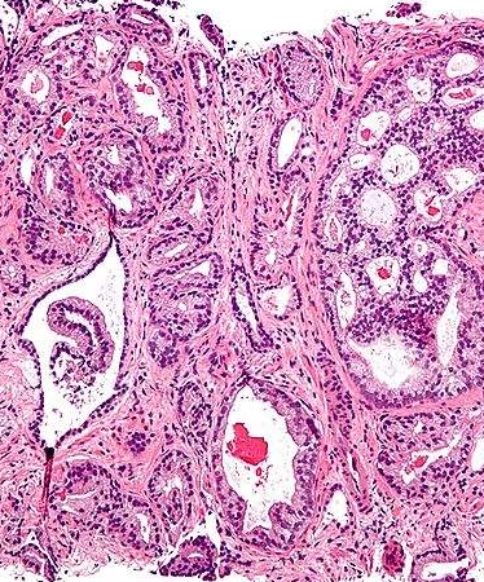

日本乳腺癌治疗 开发新一代乳腺癌靶向药